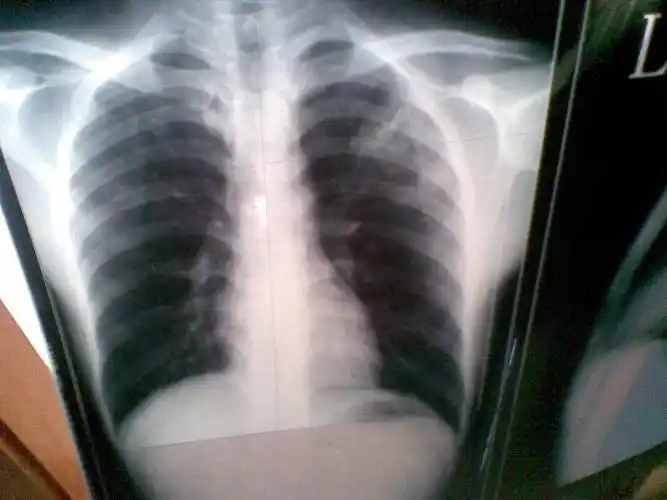

因为工作要去体检 结果检查说有左上浸润型肺结核.